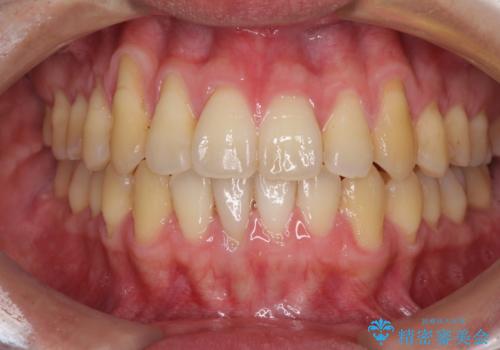

- 上下の前歯の反対咬合を気にして来院された患者様です。

インビザラインを用い、下顎はIPR(歯と歯の間を削る)と歯列全体を後方に移動させ、上顎は前歯を持ち上げることで、反対咬合を改善していくこととしました。

八重歯の歯根が見えている点も気になっているので、矯正歯科治療後に歯肉移植による根面被覆を行うこととしました。

インビザラインによる反対咬合の改善は、上の歯が下の歯を乗り越えていく期間に咬み合わせが非常に不安定となり、治療が長期化することがあります。

また、ワイヤー矯正と異なり歯軸改善の強い力を前歯にかけるため、反対咬合で裏側にある歯の歯肉が退縮しやすくなります。

矯正治療により元々気になっていた八重歯と、反対咬合が改善された歯の2本に対して根面被覆を行い、審美面の改善も達成しました。